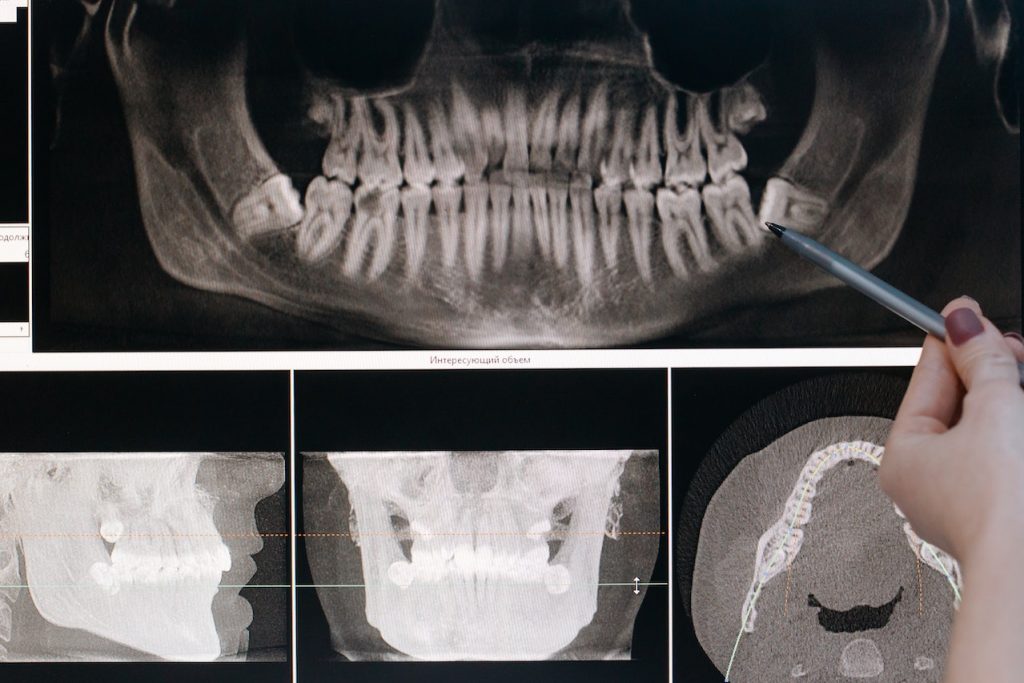

Nuestro equipo de especialistas en implantología tiene una amplia experiencia en la colocación de implantes dentales, utilizando técnicas quirúrgicas precisas y tecnología de imagen avanzada para garantizar una integración sólida y una restauración natural. Con nuestros implantes dentales, disfrutará de una sonrisa completa y funcional, que se sentirá y lucirá como sus dientes naturales.

En casos en los que el hueso del maxilar superior es insuficiente para la colocación de implantes dentales, realizamos una elevación del seno maxilar. Este procedimiento consiste en elevar el seno maxilar y agregar injerto óseo para aumentar el volumen y la calidad del hueso.

Nuestro equipo de especialistas en implantología está altamente capacitado en la realización de elevaciones del seno maxilar, utilizando técnicas avanzadas y materiales de injerto de calidad para lograr resultados óptimos. Con la elevación del seno maxilar, podemos crear una base sólida para la colocación de implantes dentales en el maxilar superior.